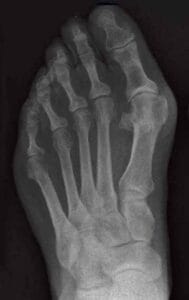

Ook tenen en nagels hebben we in alle soorten en maten, van gewone tenen tot hamertenen, klauwtenen en klauwnagels (zeer verdikte nagel die er uitziet als een ramshoorn en daarom ook wel ramshoornnagel genoemd wordt), ruitertenen, dwarsliggende kleine tenen en de hallux valgus (scheefgroei grote teen), verdikte nagels, tunnelnagels (tunnelvorm) en schimmelnagels . Kortom, elke voet, teen en nagel is uniek. Net zoals mensen dat zelf zijn.

Het ontstaan van standsafwijkingen en andere aandoeningen aan voeten, tenen en nagels kan verschillende oorzaken hebben. Ze kunnen gewoon aangeboren zijn, ontstaan door ziekten als reuma en diabetes of andere problemen elders in het lichaam, waardoor je, vaak ongemerkt, anders gaat lopen. Maar ook door het dragen van te nauwe schoenen, die niet goed bij de vorm van je voeten passen. Een voorbeeld is de hallux valgus, de scheefgroeiende grote teen (hallux betekent: grote teen). Door botwoekering in het middenvoetsbeentje dat direct vóór de grote teen ligt ontstaat een knobbel en gaat de grote teen scheef groeien. Het ontstaan van de botwoekering kan aangeboren zijn, maar ook veroorzaakt worden door het dragen van schoenen met een hoge hak, zoals pumps, waardoor het lichaamsgewicht op de voorvoet komt te liggen en de tenen bij elkaar worden geperst in de puntige neus van de schoen. Een hallux valgus komt vaker voor bij vrouwen dan bij mannen en kan flink pijn doen. Door de wrijving en irritatie op o.a. de grote teen reageert het lichaam met het aanmaken van extra bot, waardoor de knobbel ontstaat en de grote teen opzij wordt gedrukt. De andere teentjes komen vervolgens ook in de knel. Je ziet dan nog wel eens dat één van de kleine teentjes over de naastliggende kleine teen gaat liggen (ruiterteen). Door druk en wrijving op de tenen kunnen daar weer eelt en pijnlijke likdoorns ontstaan.